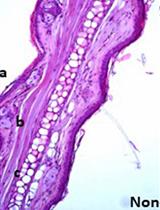

The microbiome plays critical roles in modulating tissue-specific immune responses particularly at barrier sites (Belkaid and Harrison, 2017). In these barrier environments, such as the gastrointestinal tract and skin, select commensals are shown to be able to drive the development of specific immune cell populations (Ivanov et al., 2009; Naik et al., 2012). Our work has recently started to explore the influence of the oral microbiome in tailoring tissue immunity, particularly at the gingiva, a vulnerable oral barrier site (Abusleme and Moutsopoulos, 2016; Dutzan et al., 2017).

In humans, it is well recognized that the oral cavity harbors a diverse and rich microbiome (Human Microbiome Project, 2012). Alterations in oral microbial communities have been associated with the common oral disease, periodontitis, an inflammatory condition that affects the gingival tissues and results in tissue damage (Griffen et al., 2012; Abusleme et al., 2013; Moutsopoulos et al., 2015). To date, animal models have been instrumental in addressing the role of the microbiome in various physiological and pathological conditions (Turnbaugh et al., 2006; Kostic et al., 2013). However, studies of host-microbiome interactions have been increasingly challenging in the oral murine setting. To facilitate oral microbiome studies in murine models, we have developed protocols for sampling of oral microbial communities, processing of low biomass murine oral microbiome samples, 16S rRNA gene sequencing and analysis of relevant data.